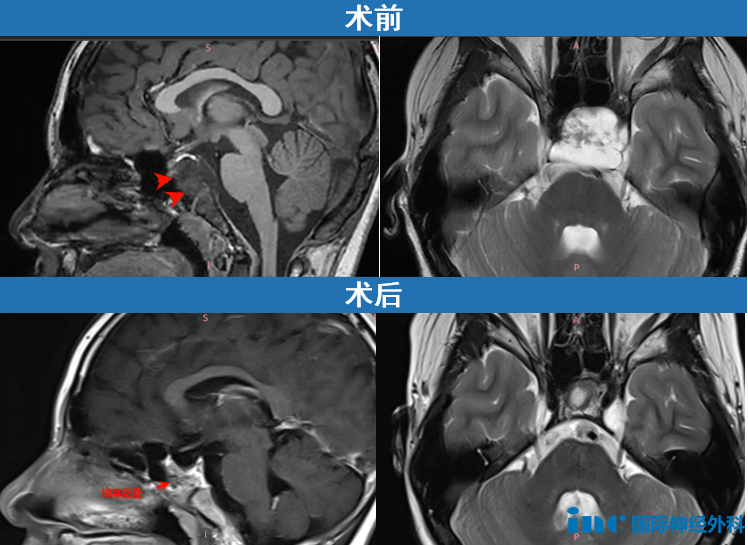

“这很有可能是一个斜坡嵴索瘤,现在有33×26×33mm这么大,已经侵袭左侧海绵窦,导致垂体移位、垂体柄歪斜,但手术风险很大,家属要慎重考虑。”

隔天,手术顺利,小海的斜坡嵴索瘤成功全切,他只需要在ICU过渡一夜后就能转回普通病房。

术后,小海的恢复始终很好,在术后四个月的随访中,福教授表示:“MRI结果在我看来非常理想,鼻腔结构完全正常,我未见明显的肿瘤残留。”